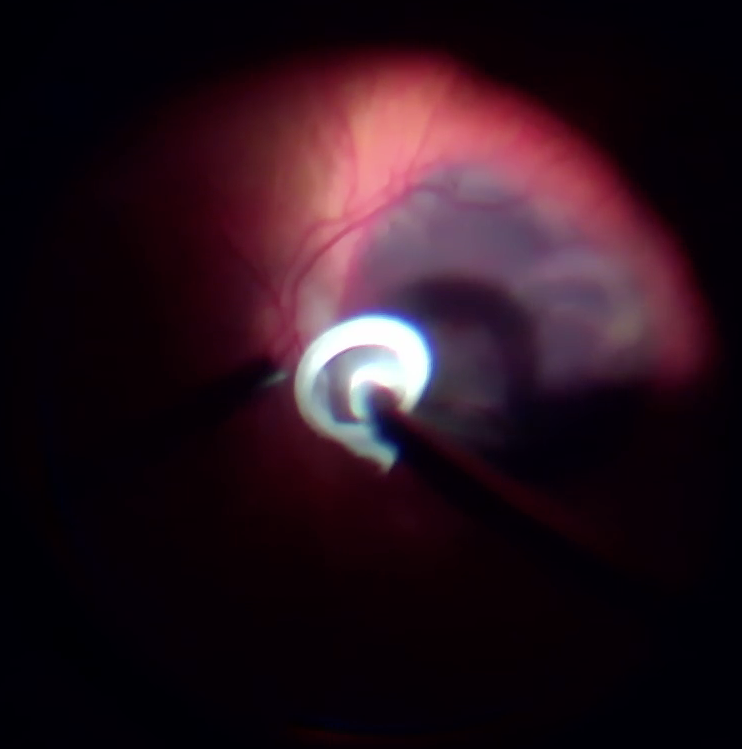

В операційній перше, що привернуло увагу - це щільна адгезія скловидного тіла до сітківки, але це питання було вирішено вітреотомом та кеналогом.

Після діатермії було виконано дренуючу ретинотомію на межі крововиливу (можна було би ще ближче до центру, але не хотілося потім виконувати лезеркоагуляцію поблизу до СНМ) та частково роздреновано субретинальній простір.

В подальшому з використанням пухиря ПФОС на сітківці та пухиря стерильного повітря під сітківкою виконано розрідження та дислокація субретинального крововиливу з аспірацією рідкого гему крізь дренуючу ретинотомію.

Лазеркоагуляція та тампонада вітреальної порожнини газовою сумішшю.

Під час операції вдалося відмити значну частину субретинальної крові, що дає право сподіватися на збереження макулярних функцій, разом з цим, згорток крові, що знаходився під сітківкою протягом 3 тижнів, вже почав фіброзуватися - такі тяжі видалити не вдалося. Ми розраховуємо на те, що такі тяжі розташовуються ближче до аркад, тому на фовеолярні функції впливати не повинні.